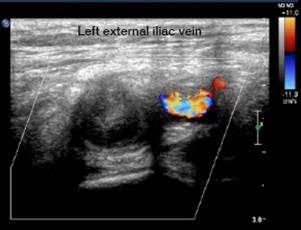

The Doppler ultrasound of the lower limb showed thrombosis of the external iliac and left common femoral veins (Figures 2 and 3). The chest x-ray, performed due to suspicion of septic pulmonary embolism, showed acinar nodule lesions (Figure 4). The CT scan showed pulmonary and subpleural nodules (Figure 5), and a D-dimer value of200-00 ng/dL was determined (reference <200). Consequently, it was confirmed that the patient had venous thromboembolism and septic pulmonary embolism. Echocardiogram and abdominal ultrasound were normal. The treatment with oxacillin was continued and the new blood cultures, taken after five days, were negative. The patient completed 42 days of antibiotic and anticoagulant treatment, and was discharged with satisfactory evolution.

Left external iliac vein thrombosis.

Figure 3: Left external iliac vein thrombosis.

Source: Document obtained during the study.